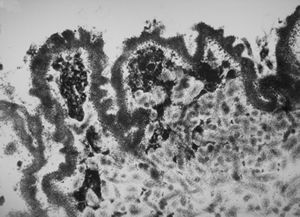

F,50y. | progressive multifocal leukoencephalopathy- viral particles in a glial cell

F,50y. | progressive multifocal leukoencephalopathy- viral particles in a glial cell

F,50y. | progressive multifocal leukoencephalopathy- viral particles in a glial cell